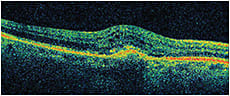

Visual acuity measured 20/100+1 OD and 20/25-2 OS. Fluorescein angiography revealed a subfoveal classic choroidal neovascular membrane with leakage OD. Figure 1 shows his OCT at baseline. He received three monthly bevacizumab injections OD with limited response in vision and on OCT, (Figures 2-3). He then received aflibercept OD. Despite missing a monthly appointment, the patient had noted improvement in vision at 2 months after injection, and the examination documented improvement in visual acuity and macular thickness on OCT (Figure 4).

Figure 1. OD at baseline, VA 20/100+1, CMT 423.